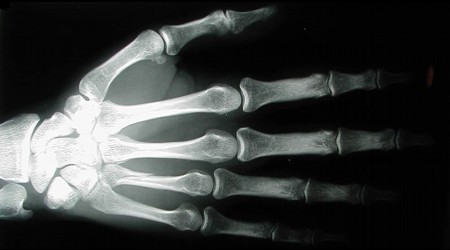

Mas, afinal, o que exatamente provoca o estalido ao puxar ou apertar os dedos? Em primeiro lugar, saiba que entre um osso e outro da mão ou de qualquer outra parte do corpo existe uma cápsula (um globo de tecido, que conhecemos como articulação) que contém um líquido em seu interior, chamado sinovial. Toda essa estrutura é reforçada pelos ligamentos.

“Puxar os dedos gera uma espécie de vácuo intra-articular que faz o líquido sinovial se movimentar com violência, daí o ruído”, descreve o ortopedista Nelson Trombini, do Hospital São Luiz Jabaquara. Essas bolhas no fluido das articulações, portanto, são a origem do estalido, um processo chamado de “cavitação”.

“Outro tipo de ruído ocorre quando dobramos uma articulação”, diferencia Trombini. Sabe aquele “cleck” que nos faz lembrar que estamos ficando enferrujados? “Nesse caso, o estalido se deve ao atrito entre as cartilagens dos ossos, ou então ao contato do tendão com alguma saliência óssea”, avisa o médico.